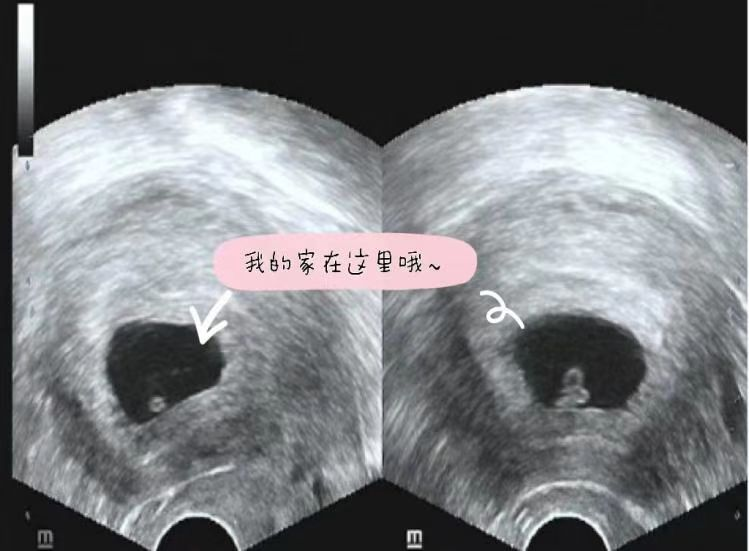

什么是异位妊娠?

异位妊娠的不同部位

95%为输卵管妊娠

迷路的宝宝